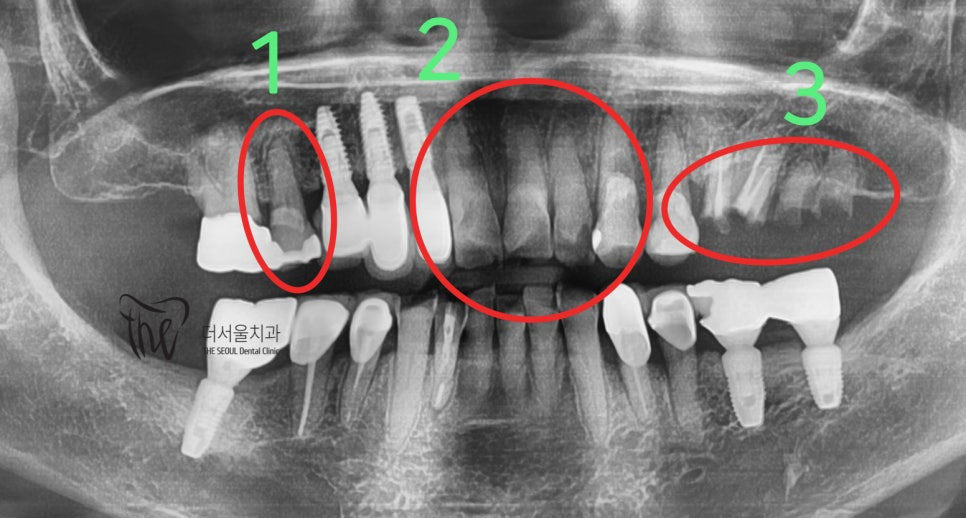

임플란트 흔들림 에는 여러가지 이유가 있습니다. 1) 잘못 된 시술 접근. 2) 환자의 부주의. 3) 흡연 및 과음. 4)

어금니쪽과 다르게 앞니 쪽에는 치아 뿌리를 감싸고 있는 치조골의 폭경이 좁습니다. 즉, 추후 임플란트 를 심으려 했을 때 충분한

네비게이션 임플란트 1) 3D 스캔 데이터, CT 데이터를 머징 시켜서 술자가 한 눈에 진단을 내리기 편하게 만든 진단 방식중에